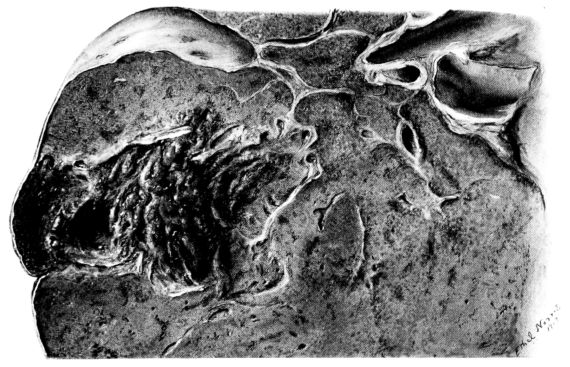

The consolidated areas vary greatly in size and number;[10] often they are small and involve only single lobules, which now stand out as granular, generally elevated patches on the surrounding congested plane. Their color, as on the pleura, varies. They may be dark, almost hemorrhagic, fading through the reds, pinks, and greys. They may be firm, or, at the other extreme, honeycombed by small, often narrow, cavities, from which a material similar to that described on the surface wells forth. The latter change is more frequent if the consolidated area is large. It has occurred most often in the pseudolobar and in the lobar types of the process. The pseudolobar change is differentiated, not only by the confluence of more or less definite lobular patches and by its involvement of portions of contiguous lobes rather than a single lobe, but also by variations in the color and consistence of the different lobular foci. This is in contrast with lobar involvement where the entire lobe is affected by a uniform process usually at the same stage of development. Although the consistence may vary in different portions, usually the same color is present throughout. (Compare Figs. XIV and XXVIII.) In one instance where a solid, yellow lobe was found, its center contained an irregular, fresh blood clot (Fig. XVIII), which would be sufficient to differentiate this type of consolidation from that of respiratory disease in which the initial lesion is less destructive. Sometimes the softening in a hepatized lobule or group of lobules is much more evident, and the zone becomes divided by irregular channels filled with viscid, grey or brown material (108, 149, 162). When such a condition lies just beneath the pleural surface, it may be distinctly seen from without (Fig. XXXIII). The pleura bulges, the normal topography of the local zone is lost, and it appears as a dull, somewhat projecting, circumscribed patch, two or three or more centimeters in diameter, the surface of which has a more or less characteristic brown or brownish black opacity. As soon as this is sectioned there pours from the cavity the liquefied exudate in which the destroyed pulmonary parenchyma is mixed (Fig. XXXIV). Occasionally, strands of tissue still traverse the cavity, but, as a rule, it empties itself completely, and leaves a brownish black wall. The delicate, sweet but persistent and penetrating odor is not so marked as with typical gangrene.

From this intermediary stage the picture of actual abscess with mortification of bronchiolar and alveolar tissue, as well as of the exudate itself, is readily approached (25, 48, 110, 140) (Fig. XXXI). In the necrotic mass that forms the center of such a focus, the most prominent feature is the bacteria. With hematoxylin they stain intensely as black, 26irregular masses, and their prominence is accentuated by the homogeneous staining qualities (with eosin) of the dead tissue, whether lung or exudate (Fig. XXXII). These abscesses may have central cavities which represent a discharge of their contents and may indicate the position of a bronchiole (Fig. XXXI). The necrosis of the alveolar walls, focal in its distribution as previously described, suggests itself as a forerunner of the more extensive necrosis encountered at this stage.

The most extreme form of mortification is seen in the wall of a gangrenous cavity, and several layers can be distinguished there. Beginning with that portion of the lung the least involved, the lesion may be limited to congestion of the alveolar wall with a serofibrinous exudate in the lumen, but this stage passes rather rapidly into another where cellular exudate, chiefly of polymorphonuclear leucocytes, predominates. Moreover, the leucocytes form not only the bulk of the alveolar content, but also distend the vessels and accumulate in the interstitial tissue around blood vessels and lymphatics. Passing toward the center of the gangrenous cavity, the lung rapidly changes in appearance. The blue zone of leucocytic infiltration makes more conspicuous the inner area of necrosis—where nuclei no longer stain and the alveolar wall is a homogeneous pink.

Gradually this phantom architecture, spotted only here and there with disintegrating polymorphonuclear leucocytes, ends in a ragged compressed border of a shaggy pink material which has no identifying qualities (Fig. XXXV). In the inner zone of pink an occasional vessel or, at times, a bronchiole more resistant to the process remains; frequently it is accentuated by the presence of partially destroyed polymorphonuclear leucocytes at its periphery. Probably these cells invade the necrotic areas along the sheath of the bronchus or vessel and not across the dead area. The thrombotic process described in the previous stage (Fig. LII) associated with an acute arteriolitis, may be associated with these gangrenous areas as well as with infarcts (82), but more likely gangrene is preceded by the acute diffuse necrosis of the alveolar wall which occurs in the fulminating cases. Furthermore, this is suggested where a typical grey hepatization is associated with marked thinning, but not actual disappearance, of the alveolar wall. Before concluding the description of this stage of the disease, mention should be made of the granular nodules of fibrin superimposed upon the swollen pleural cells and also of the older pleural exudate, either typically fibrinopurulent or more homogeneous with broken nuclear fragments (Fig. XXXVIII).